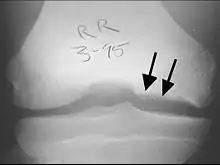

X-rays show lucency of the ossification on the anterior aspect of the knee in juvenile patients. In older people, the lesion typically appears as an area of osteosclerotic bone with a radiolucent line between the osteochondral defect and the epiphysis. The visibility of the lesion depends on its location and on the amount of knee flexion used. Harding described the lateral X-ray as a method to identify the site of an OCD lesion.[36]